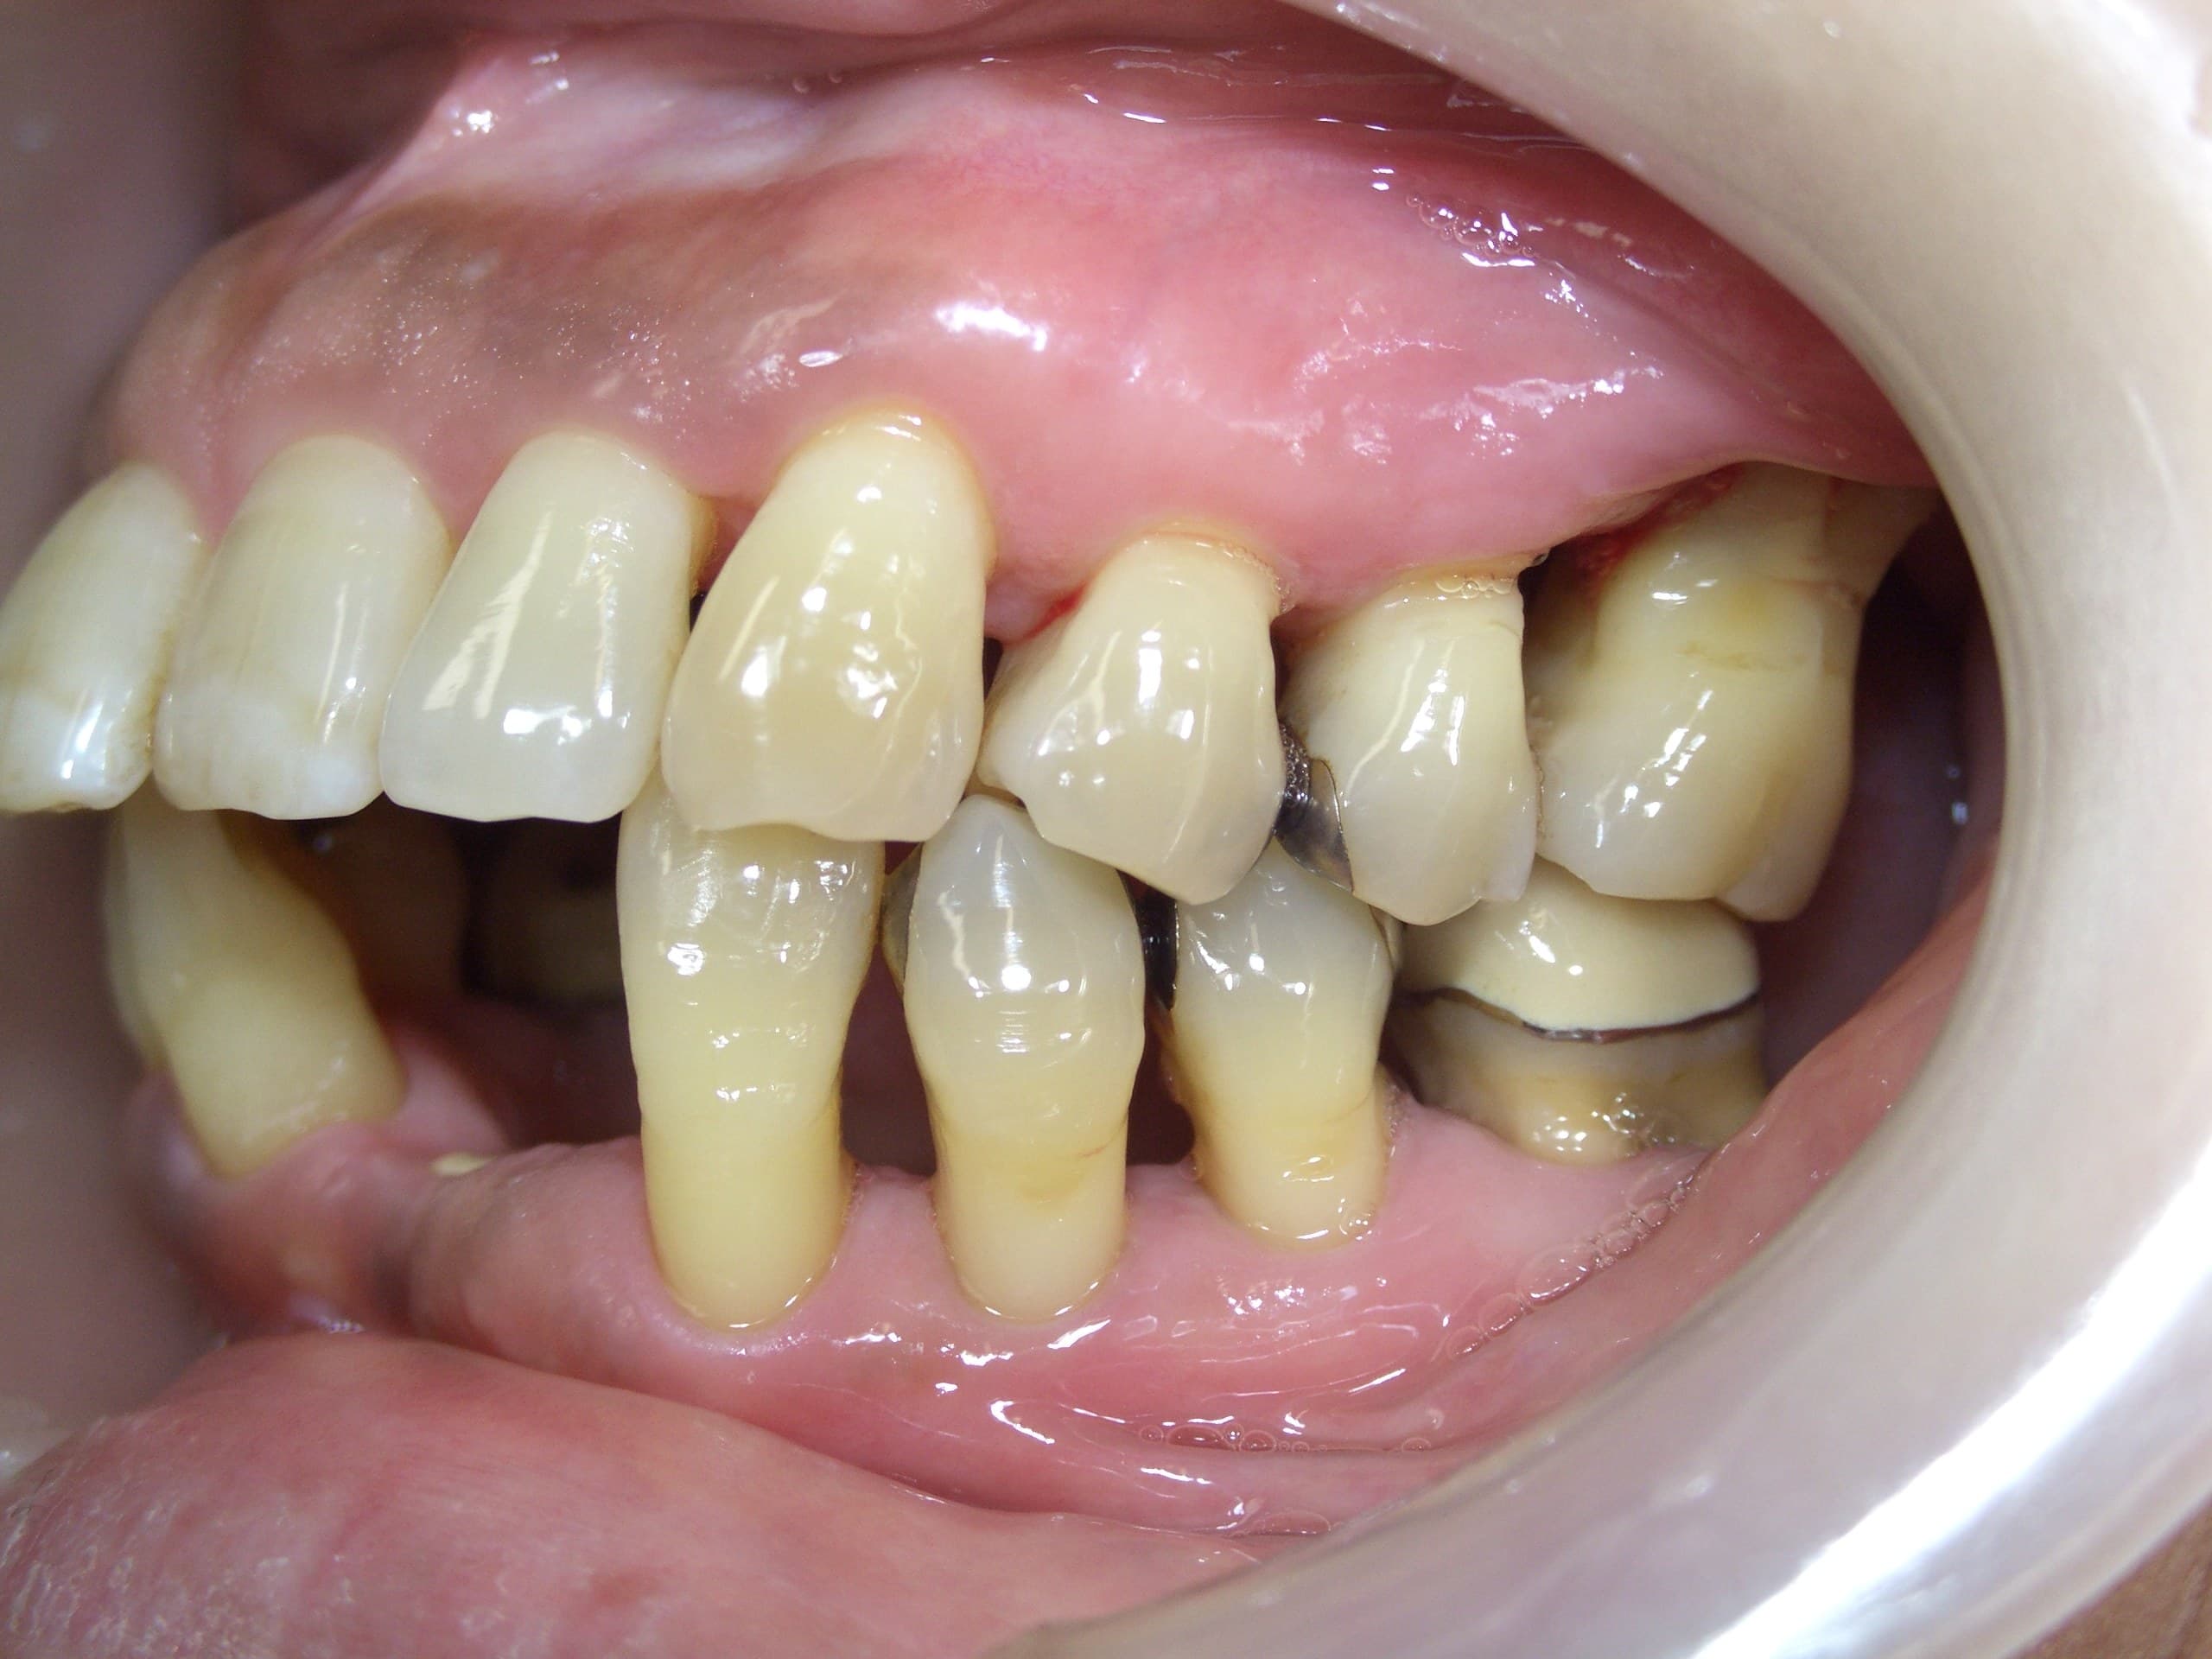

歯周病治療を行った症例をご紹介します。

50代の女性の方です。

以前から歯がぐらついてきて、そのたびに歯医者に通い歯を抜いていたそうです。

治療に行く度に抜歯をする中で、「どうしても、自分の歯で生活をしたい」という思いが芽生え、来院してくださいました。

重度の歯周病で、出血があり歯もグラグラして、歯周ポケットは5~8mmと深くありました。

初診時から3年経った現在も、グラグラや出血は落ち着き、大変おきれいにセルフケアを続けて頂いています。